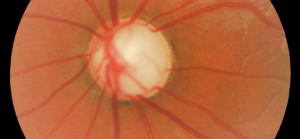

La Dra. Canut, coordinadora del Departamento de Glaucoma del Centro del Oftalmología Barraquer, define el glaucoma como: una enfermedad irreversible del nervio óptico que puede deberse a varias causas y cuyo factor de riesgo más importante es la presión intraocular elevada (PIO). La importancia de esta enfermedad se pone de manifiesto en cuanto supone la segunda causa de ceguera en los países desarrollados. La gran mayoría de los pacientes afectados de glaucomano suelen tener síntomas hasta entrar en fases avanzadas de la enfermedad y teniendo en cuenta la irreversibilidad de los daños entonces producidos, es de vital importancia diagnosticar la enfermedad en su fase más incipiente”.